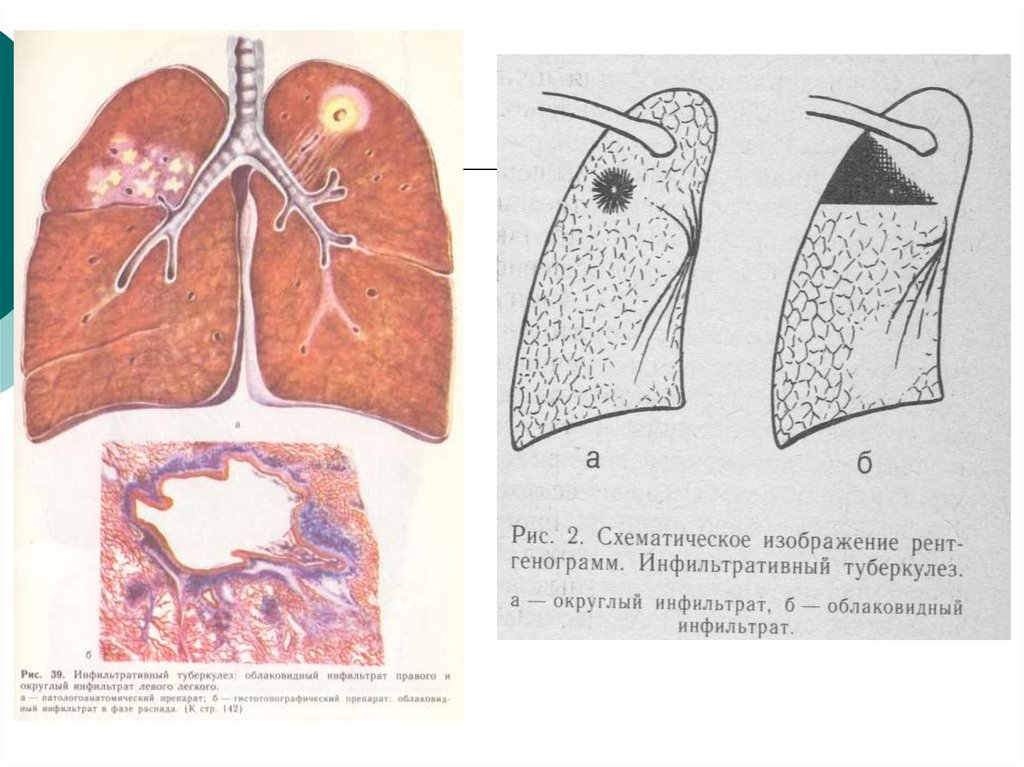

Очаговый и инфильтративный туберкулез презентация - 94 фото